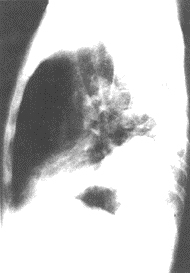

(5)X線胸片示有充血性肺不張或肺梗死,多在12~36h內出現。

X射線圖本病發病急,須做急救處理。